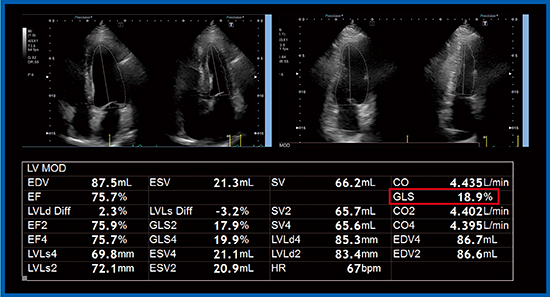

Aplio i900では,biplane disk summation法で左室容積計測を行うと,EFなどに加えてglobal longitudinal strain(GLS)が表示される(図2□:症例1)。GLSを算出する従来の手法である2D Wall Motion Tracking(WMT)(図3 b,図4)では,心内膜のラインを細かく等分し,それぞれの点の長さの変化の合計でストレインを算出する。一方,biplane disk summation法(Auto EF計測)によるGLS(図3 a)は,心内膜のトレースラインの長さの変化をストレインとして算出している。そして,4 chamber viewと2 chamber view双方の平均値から左室GLSが算出される。

症例1について,上記の2つの手法で求めたGLSの値を比較すると,いずれも18.9%であった(図5)。いずれの方法でもかなり近似した値が算出されるが,本症例は壁運動異常がないことに注意する必要がある。

図2 Biplane disk summation法によるGLSの算出(症例1)

図5 Biplane disk summation法と2D WMTによるGLSの比較